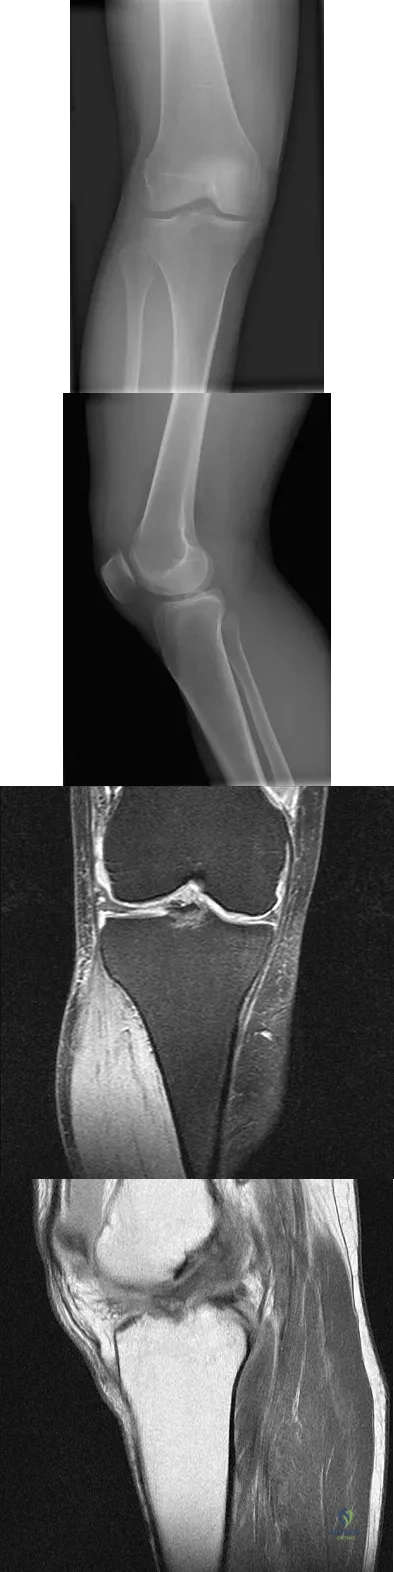

A 23-year-old woman falls from a bicycle and sustains a right knee injury. Figures 12a through 12d show radiographs and MRI scans of the knee. What is the most likely diagnosis?

Explanation